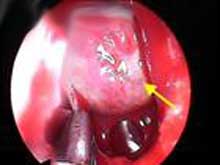

蝶鞍擴大可見於下丘腦或垂體腫瘤。微腺瘤蝶鞍無擴大但可有局限性破壞,CT或MRI有助進一步診斷。